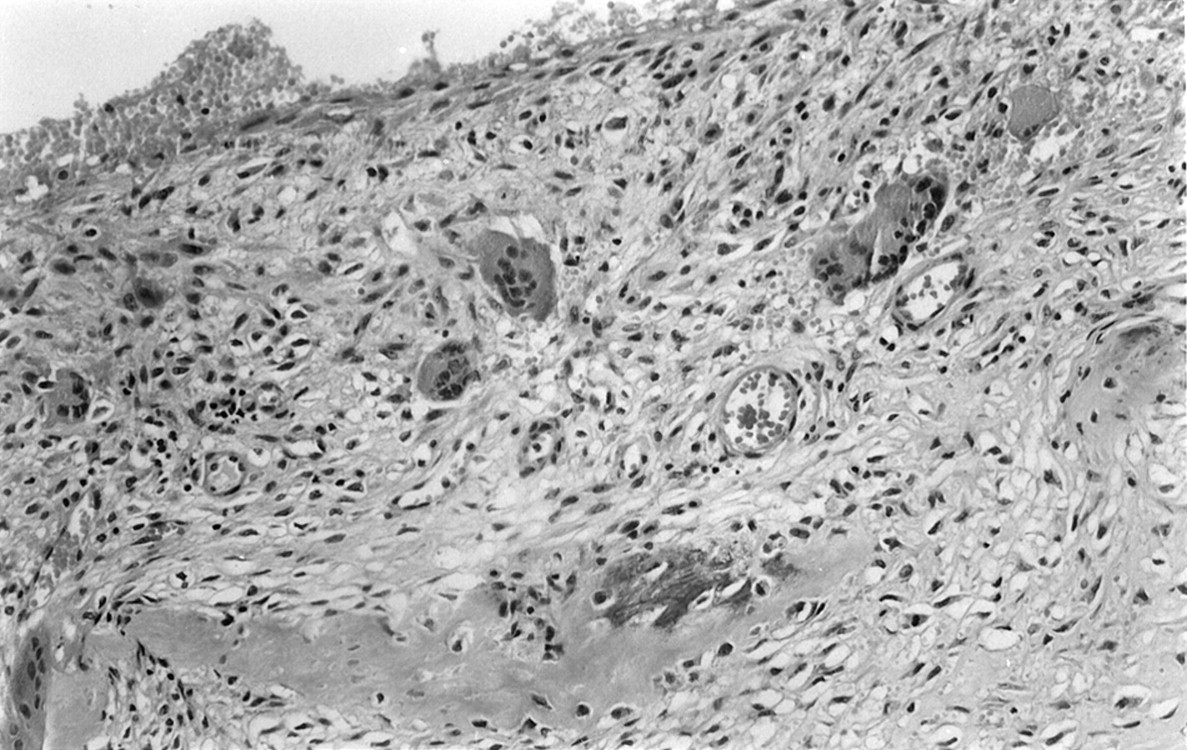

A 13-year-old female adolescent had rapidly growing, painful swelling in her right frontal region and diplopia over a 2-month period. She had no history of trauma or surgery. Physical examination revealed a firm, fixed mass situated just superior and posterior to the right orbital rim. Exophthalmos was present on the right. The lateral gaze of the right eye was restricted, but visual acuity was normal. On coronal and axial CT scans, a multiloculated mass with fluid-fluid levels was found. Bone destruction was present in the superior, lateral, and posterior walls of the right orbit (Fig 1). T1- and T2-weighted imaging revealed variable signal intensities of fluid-fluid levels, consistent with blood degradation products. The walls of the cystic spaces and surrounding rim showed contrast enhancement. The mass was compressing the optic nerve and ocular muscles inferomedially (Fig 2). A cystic mass, approximately 4.5 × 3 × 3 cm in size and containing brown-yellowish fluid, was surgically removed. Histopathologic analysis revealed multiple blood-filled cystic spaces. The borders of these spaces were lined by osteoclast type multinucleated giant cells, bone, and fibrous tissue. Endothelial cells were not present. These findings were consistent with those of an aneurysmal bone cyst (Fig 3).

Histologic specimen shows multiple giant cells and bony spicula within the walls of the cystic spaces containing erythrocytes (hematoxylin-eosin stain, magnification ×20).